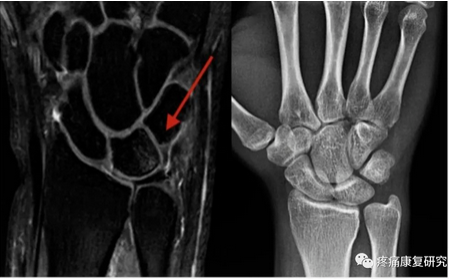

以 X 线和 MRI 检查最具价值。

X 线检查可以判断尺骨变异类型并测量变异值,发现月骨、三角骨骨质硬化和囊变,并排除骨折、腕关节炎等其他疾病。

MRI 检查可以发现月骨软骨软化及骨髓水肿等早期改变,也可以诊断 TFCC 损伤,具有较高的灵敏度和特异度。

左图MRI:显示月骨尺侧近端存在骨水肿区域;右图X线:显示尺骨正变异。